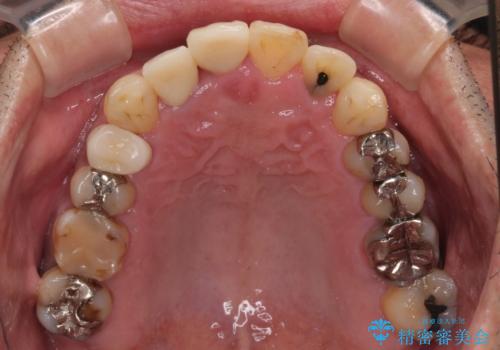

矯正治療後は、前歯や下顎の奥歯など、むし歯治療途中の歯をオールセラミッククラウンにて補綴治療を行うこととしました。

内側に転位していた前歯は、矯正治療では治しきることができませんでしたが、幸いにもオールセラミッククラウンに置き換える予定であったため、希望通りの仕上がりとなりました。